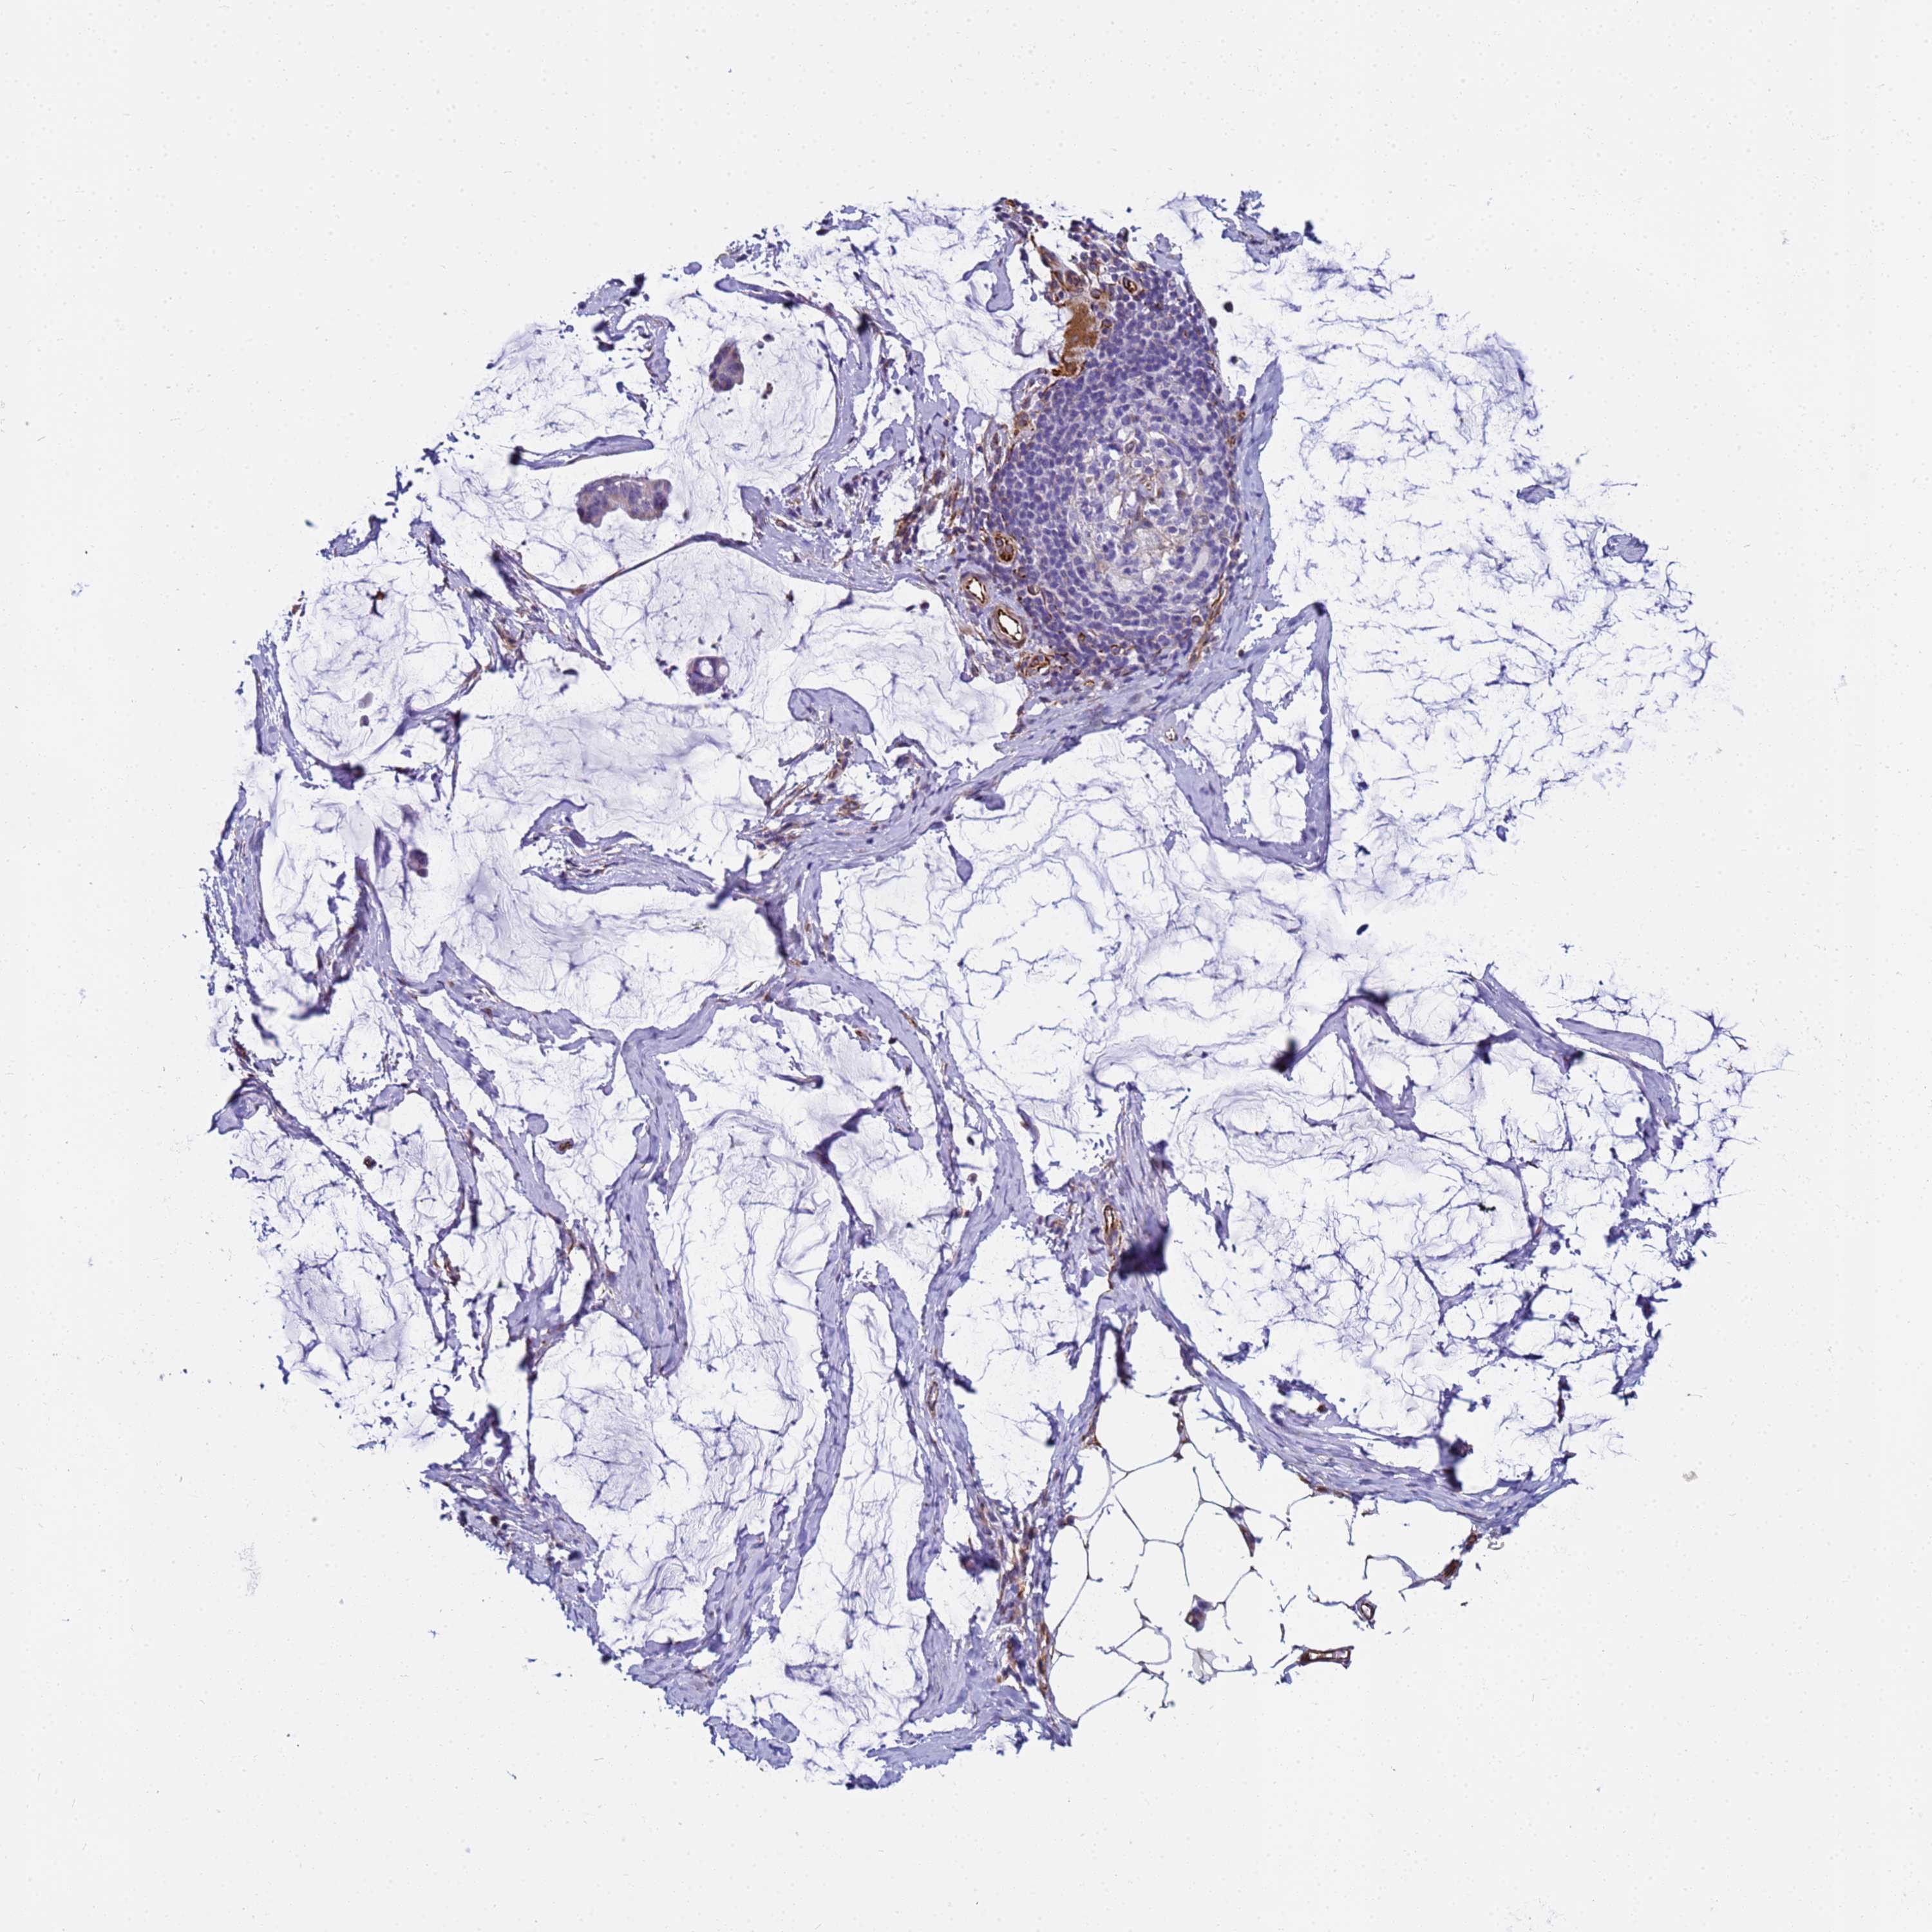

OVARIAN CANCER - Protein expressioni

A mouse-over function shows sample information and annotation data. Click on an image to view it in a full screen mode. Samples can be filtered based on level of antibody staining by selecting one or several of the following categories: high, medium, low and not detected. The assay and annotation is described here.

Note that samples used for immunohistochemistry by the Human Protein Atlas do not correspond to samples in the TCGA dataset.

Antibody stainingi

Antibody staining in the annotated cell types in the current human tissue is reported as not detected, low, medium, or high, based on conventional immunohistochemistry profiling in selected tissues. This score is based on the combination of the staining intensity and fraction of stained cells.

Each image is clickable and will lead to virtual microscopy that enables deeper exploration of all samples and also displays staining intensity scores, fraction scores and subcellular localization as well as patient and tissue information for each sample.

Antibody HPA045278

Staining

High

Medium

Low

Not detected

Intensity

Strong

Moderate

Weak

Negative

Quantity

>75%

75%-25%

<25%

None

Location

Nuclear

Cytoplasmic/membranous

Cytoplasmic/membranous,nuclear

Cystadenocarcinoma, serous, NOS

Carcinoma, endometroid

Cystadenocarcinoma, mucinous, NOS

Carcinoma, NOS